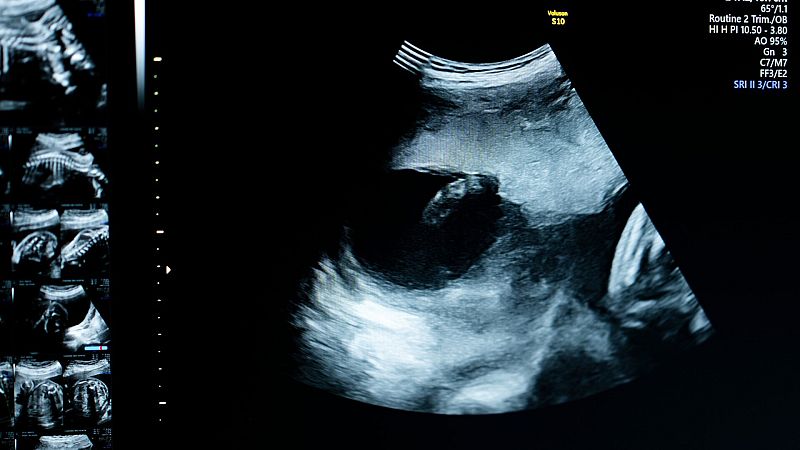

Más de 200.000 personas van a formar parte de Impact, un macroestudio que busca radiografiar el estado de salud de los españoles. Participan 50 centros de atención primaria de todas las comunidades, urbanos y rurales. Monitorizan por completo la salud de los españoles.

Después de un cuestionario exhaustivo, también se realiza una analítica de sangre. ptra de orina, una prueba de fuerza, un electrocardiograma, ecografías...

El proyecto pretende conocer la situación actual de salud de nuestra población y casi todos los factores que pueden influir en el futuro de la salud. El objetivo es predecir cuándo van a suceder las enfermedades, cuáles son los medicamentos que mejor van a funcionar y, en definitiva, la capacidad de poder anticiparnos a las enfermedades.

Los millones de datos que se obetengan se van a procesar en el supercomputador Mare Nostrum, en Barcelona. Estará continuamente alimentado porque, de momento, es un estudio sin fecha de caducidad. Aseguran que este proyecto, financiado por el Ministerio de Ciencia y para el que se han contratado profesionales específicamente, no va a interferir en el normal funcionamiento de los centros de salud.